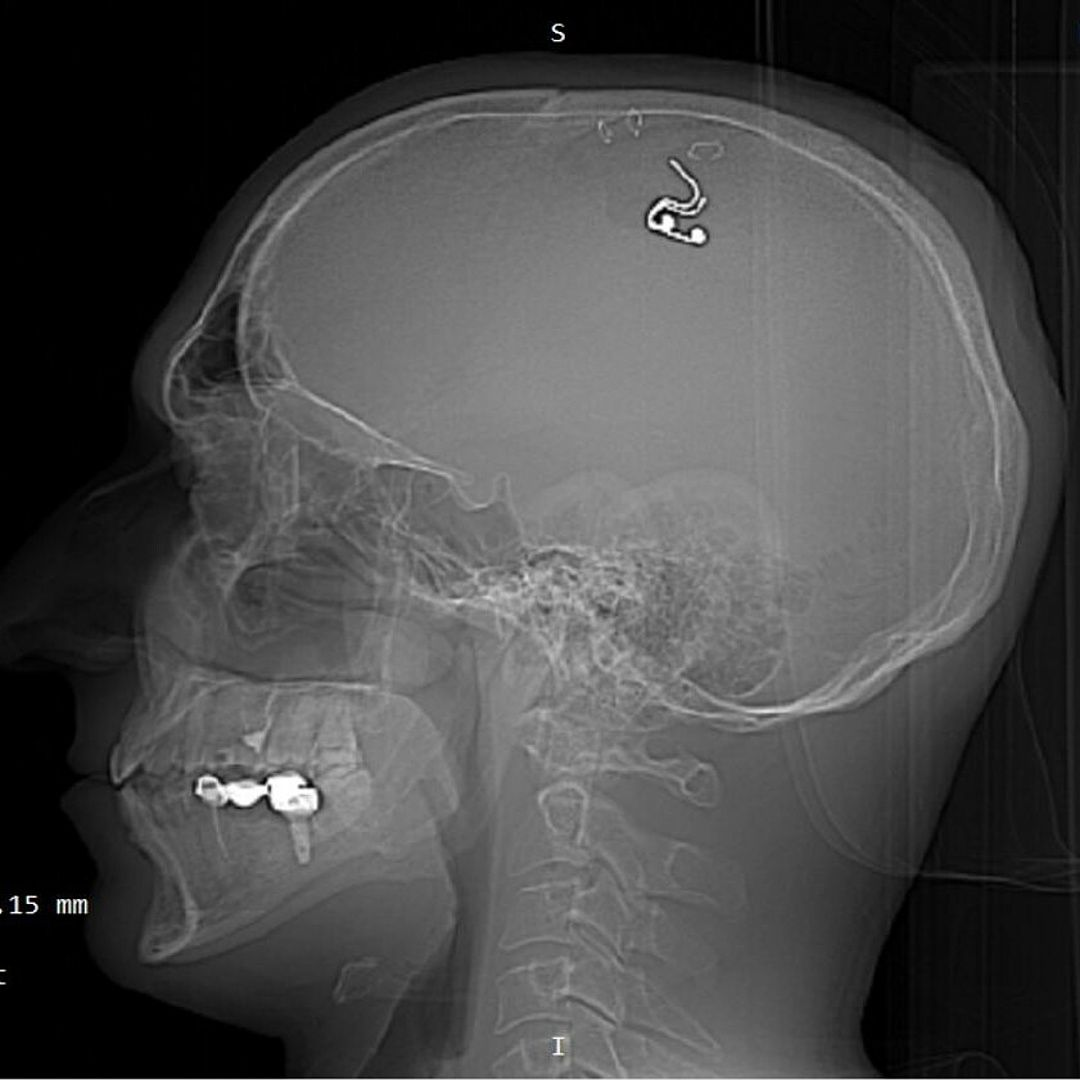

Мужчина просверлил себе череп дрелью в Алматы

- 20 Июля 2023

- 461